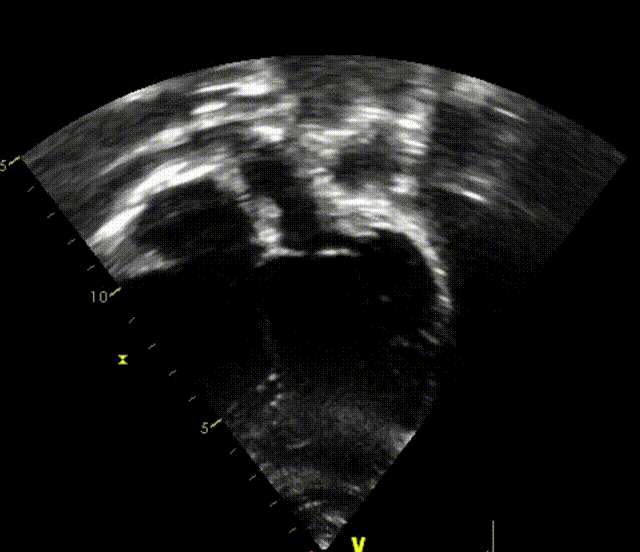

室早RFCA+ASD介入病例(上:术后6个月心超;下:术后12个月心超)

上述良好的短中期随访结果验证了可降解封堵器在儿童ASD介入治疗中的安全性与有效性,期待更长期的随访数据进一步验证远期效果。